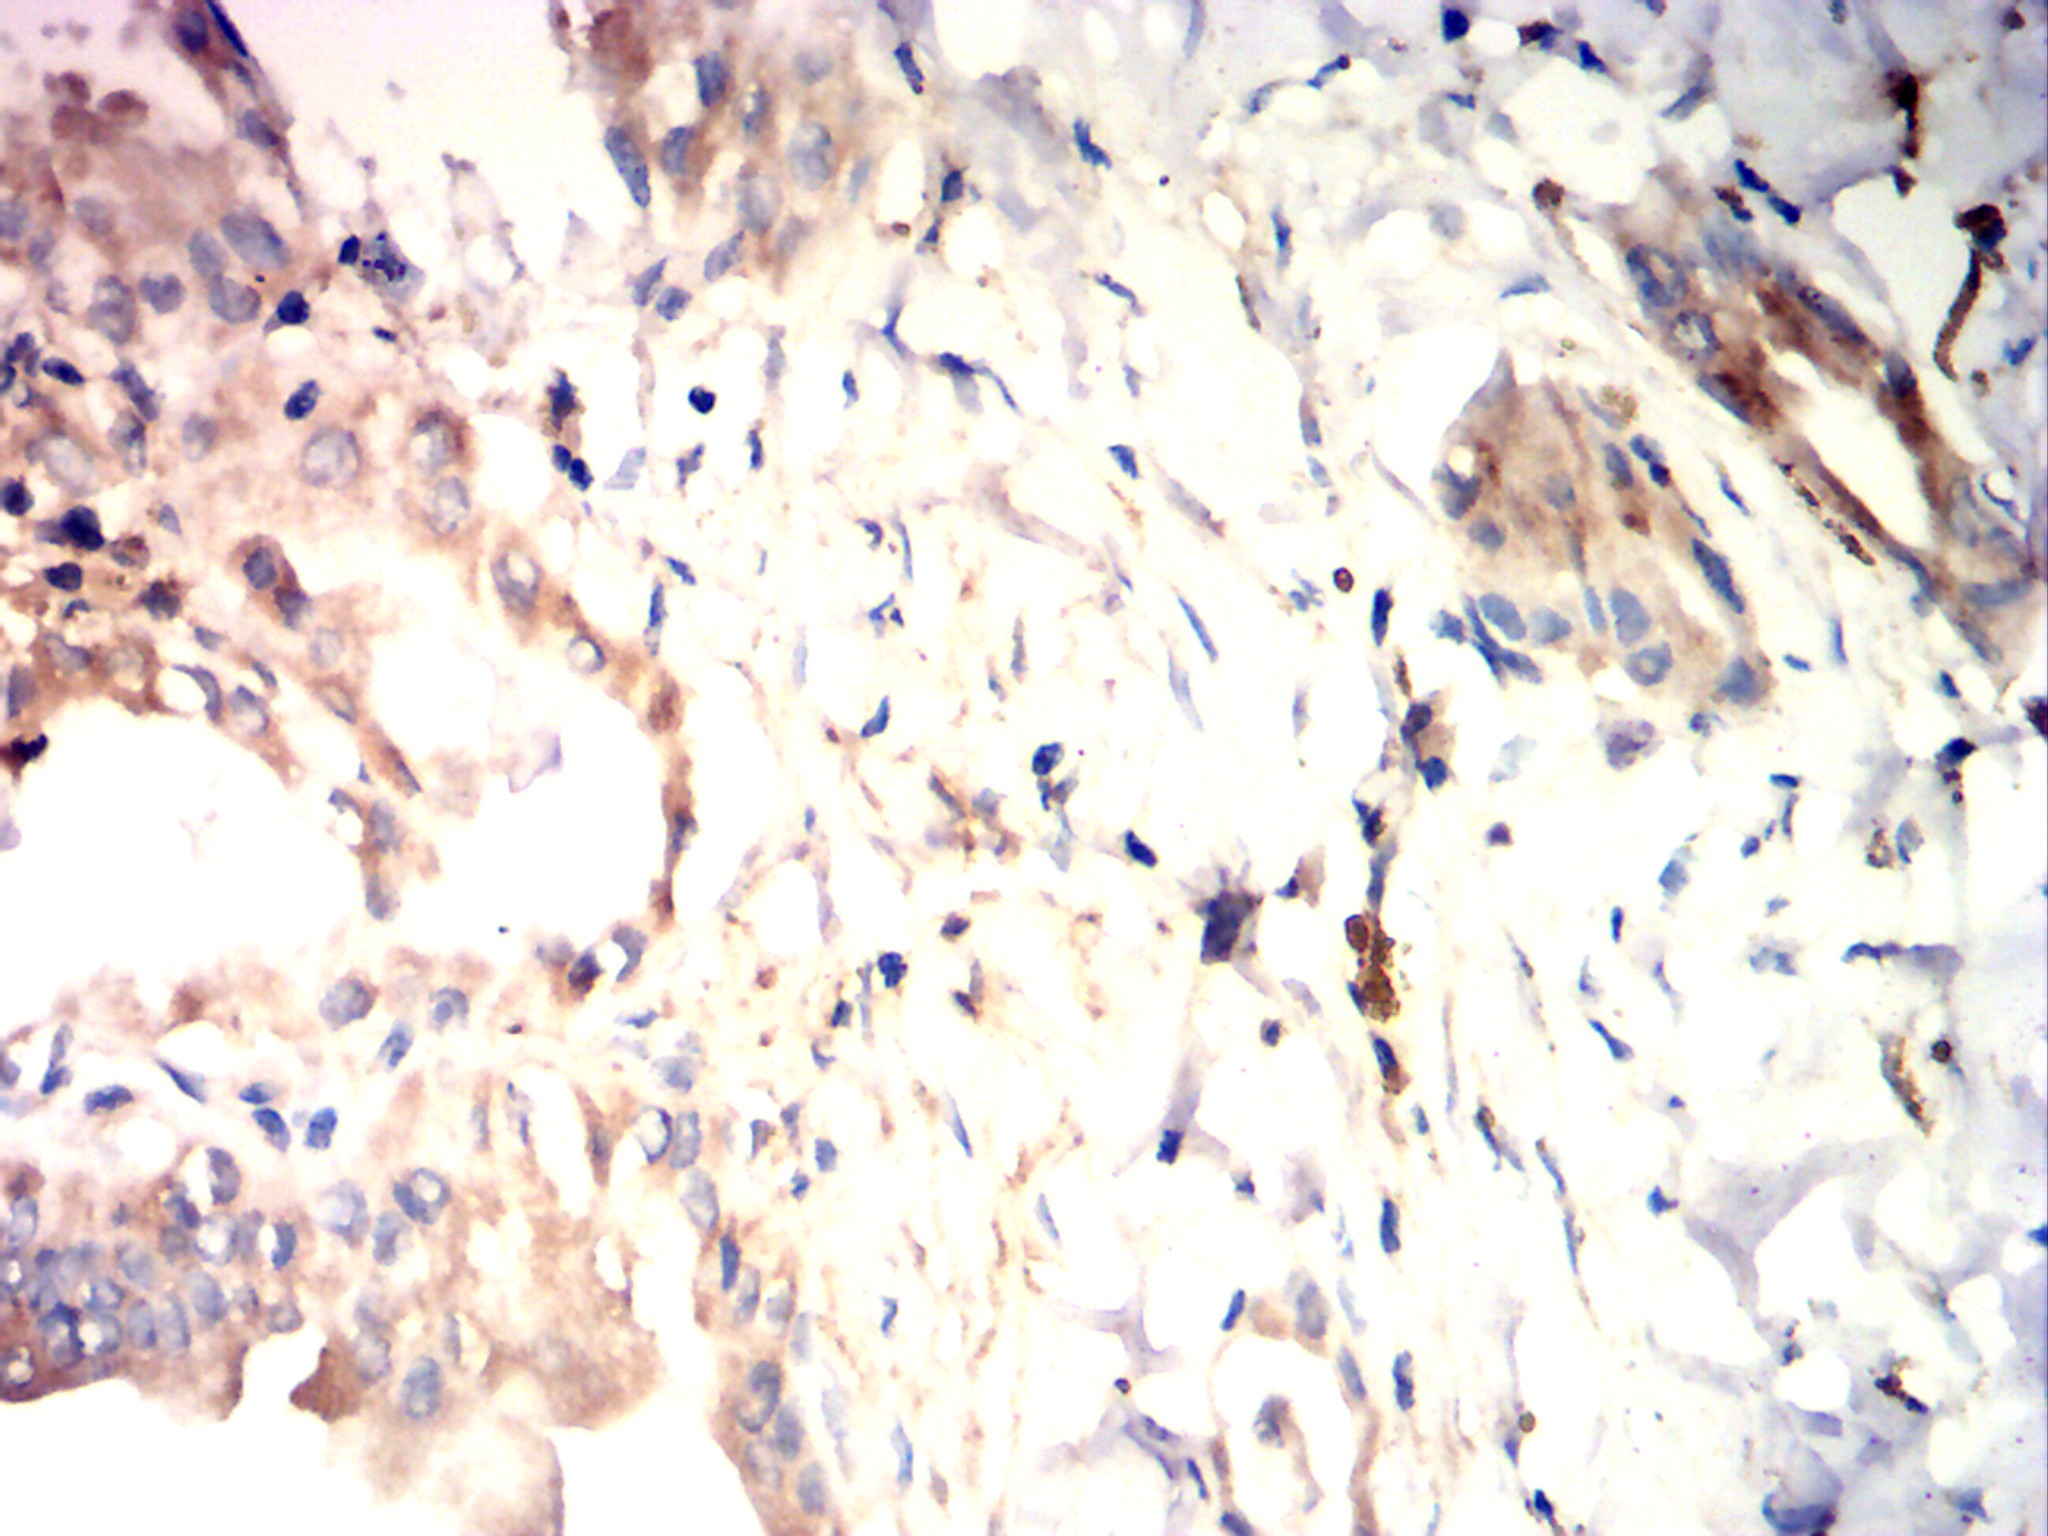

Immunohistochemical analysis of paraffin-embedded rectal cancer tissues using LSD1 antibody with DAB staining.Pre-treat the sections with heat-mediated antigen retrieval using sodium citrate buffer (pH 6.0) (OM750020) for 2 minutes. Wash the sections with ddH₂O and PBS (OM750003). Block the tissue with 10% non-immune goat serum(OM760028) at room temperature for 30 minutes. Incubate the tissue with the primary antibody diluted at a ratio of 1:1500 at 4°C overnight. At room temperature, dilute the secondary antibody, Goat Anti-Mouse IgG (H&L) - HRP(OM644366), at a ratio of 1:200 and incubate for one hour. Use DAB(OM760029)as the chromogenic agent. Counterstain the tissue with hematoxylin, and mount the tissue sections with neutral gum.WB

Immunohistochemical analysis of paraffin-embedded rectal cancer tissues using LSD1 antibody with DAB staining.Pre-treat the sections with heat-mediated antigen retrieval using sodium citrate buffer (pH 6.0) (OM750020) for 2 minutes. Wash the sections with ddH₂O and PBS (OM750003). Block the tissue with 10% non-immune goat serum(OM760028) at room temperature for 30 minutes. Incubate the tissue with the primary antibody diluted at a ratio of 1:1500 at 4°C overnight. At room temperature, dilute the secondary antibody, Goat Anti-Mouse IgG (H&L) - HRP(OM644366), at a ratio of 1:200 and incubate for one hour. Use DAB(OM760029)as the chromogenic agent. Counterstain the tissue with hematoxylin, and mount the tissue sections with neutral gum.